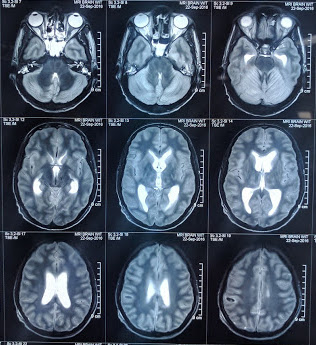

On day nine it was decided to discontinue ECMO support. All cultures were sterile so far. His legs improved and a repeat Doppler study showed normal flows on the left side and near normal flows on the right side, hence amputation was best avoided. We did MRI of the brain which showed gross cerebral edema with focal haemorrhagic spots and supratentorial ventriculomegaly with hypoxic changes in the midbrain and basal ganglia. Neurologist said that he had a very poor prognosis and opined for a tracheostomy and neurosurgery consult in view of raised intracranial tension. Neurosurgeon opined for conservative management as he had a tight brain and there was no space in the ventricles to put in an endo-ventricular drain (EVD). He remained neurologically poor (withdraws and opens eyes to painful stimulus E2M4, pupils unequal and sluggish reacting) was discharged to a smaller facility for neuro-rehabilitation (Figure 1 - Figure 4).

Figure 3 MRI Brain showing micro bleeds and midbrain hypoxic change.

Studies with VA-ECMO in children has a survival rate of 88% but in critically ill adults the favourable outcome widely varies.3 There have been recent advances in ECMO technology, which has incorporated improvement in biocompatility, monitoring and membrane lung oxygenation, but the role of VA-ECMO in septic shock is largely debated. The growing evidence and role of ECMO in peri-arrest situation has been reviewed recently4 and we used it in our patient as a final attempt, considering his young age and treatable disease condition. Over the period 2003–2014 in the ELSO registry, survival to hospital discharge was 29% for patients who require ECPR.5 In our case we used the femoral route and we faced some complications like limb ischaemia, which was appropriately managed, and we were able to salvage the limbs of our patient. The liver function per se deteriorated as he was on antitubercular drugs (pyrazinamide and rifampicin) and eventually shock contributed to low hepatic perfusion. We do not have the facility to perform thromboelastography (TEG) in our institute. The institution of VA-ECMO in our patient did improve the cardiac function in our patient dramatically within a span of one week (LVEF improved to 40%) and his lung compliance gradually improved and we were able to decrease oxygen requirements and ventilatory parameters steadily. The neurological status was a cause of concern especially in the backdrop of a hypoxic brain damage after cardiac arrest. The multiple punctate hemorrhages are typical of ECMO related CNS injury.6,7 There are several trials reporting the incidence of nosocomial infection as high as 64% while on ECMO support,8 but fortunately we had sent every alternate day blood cultures, which were sterile.